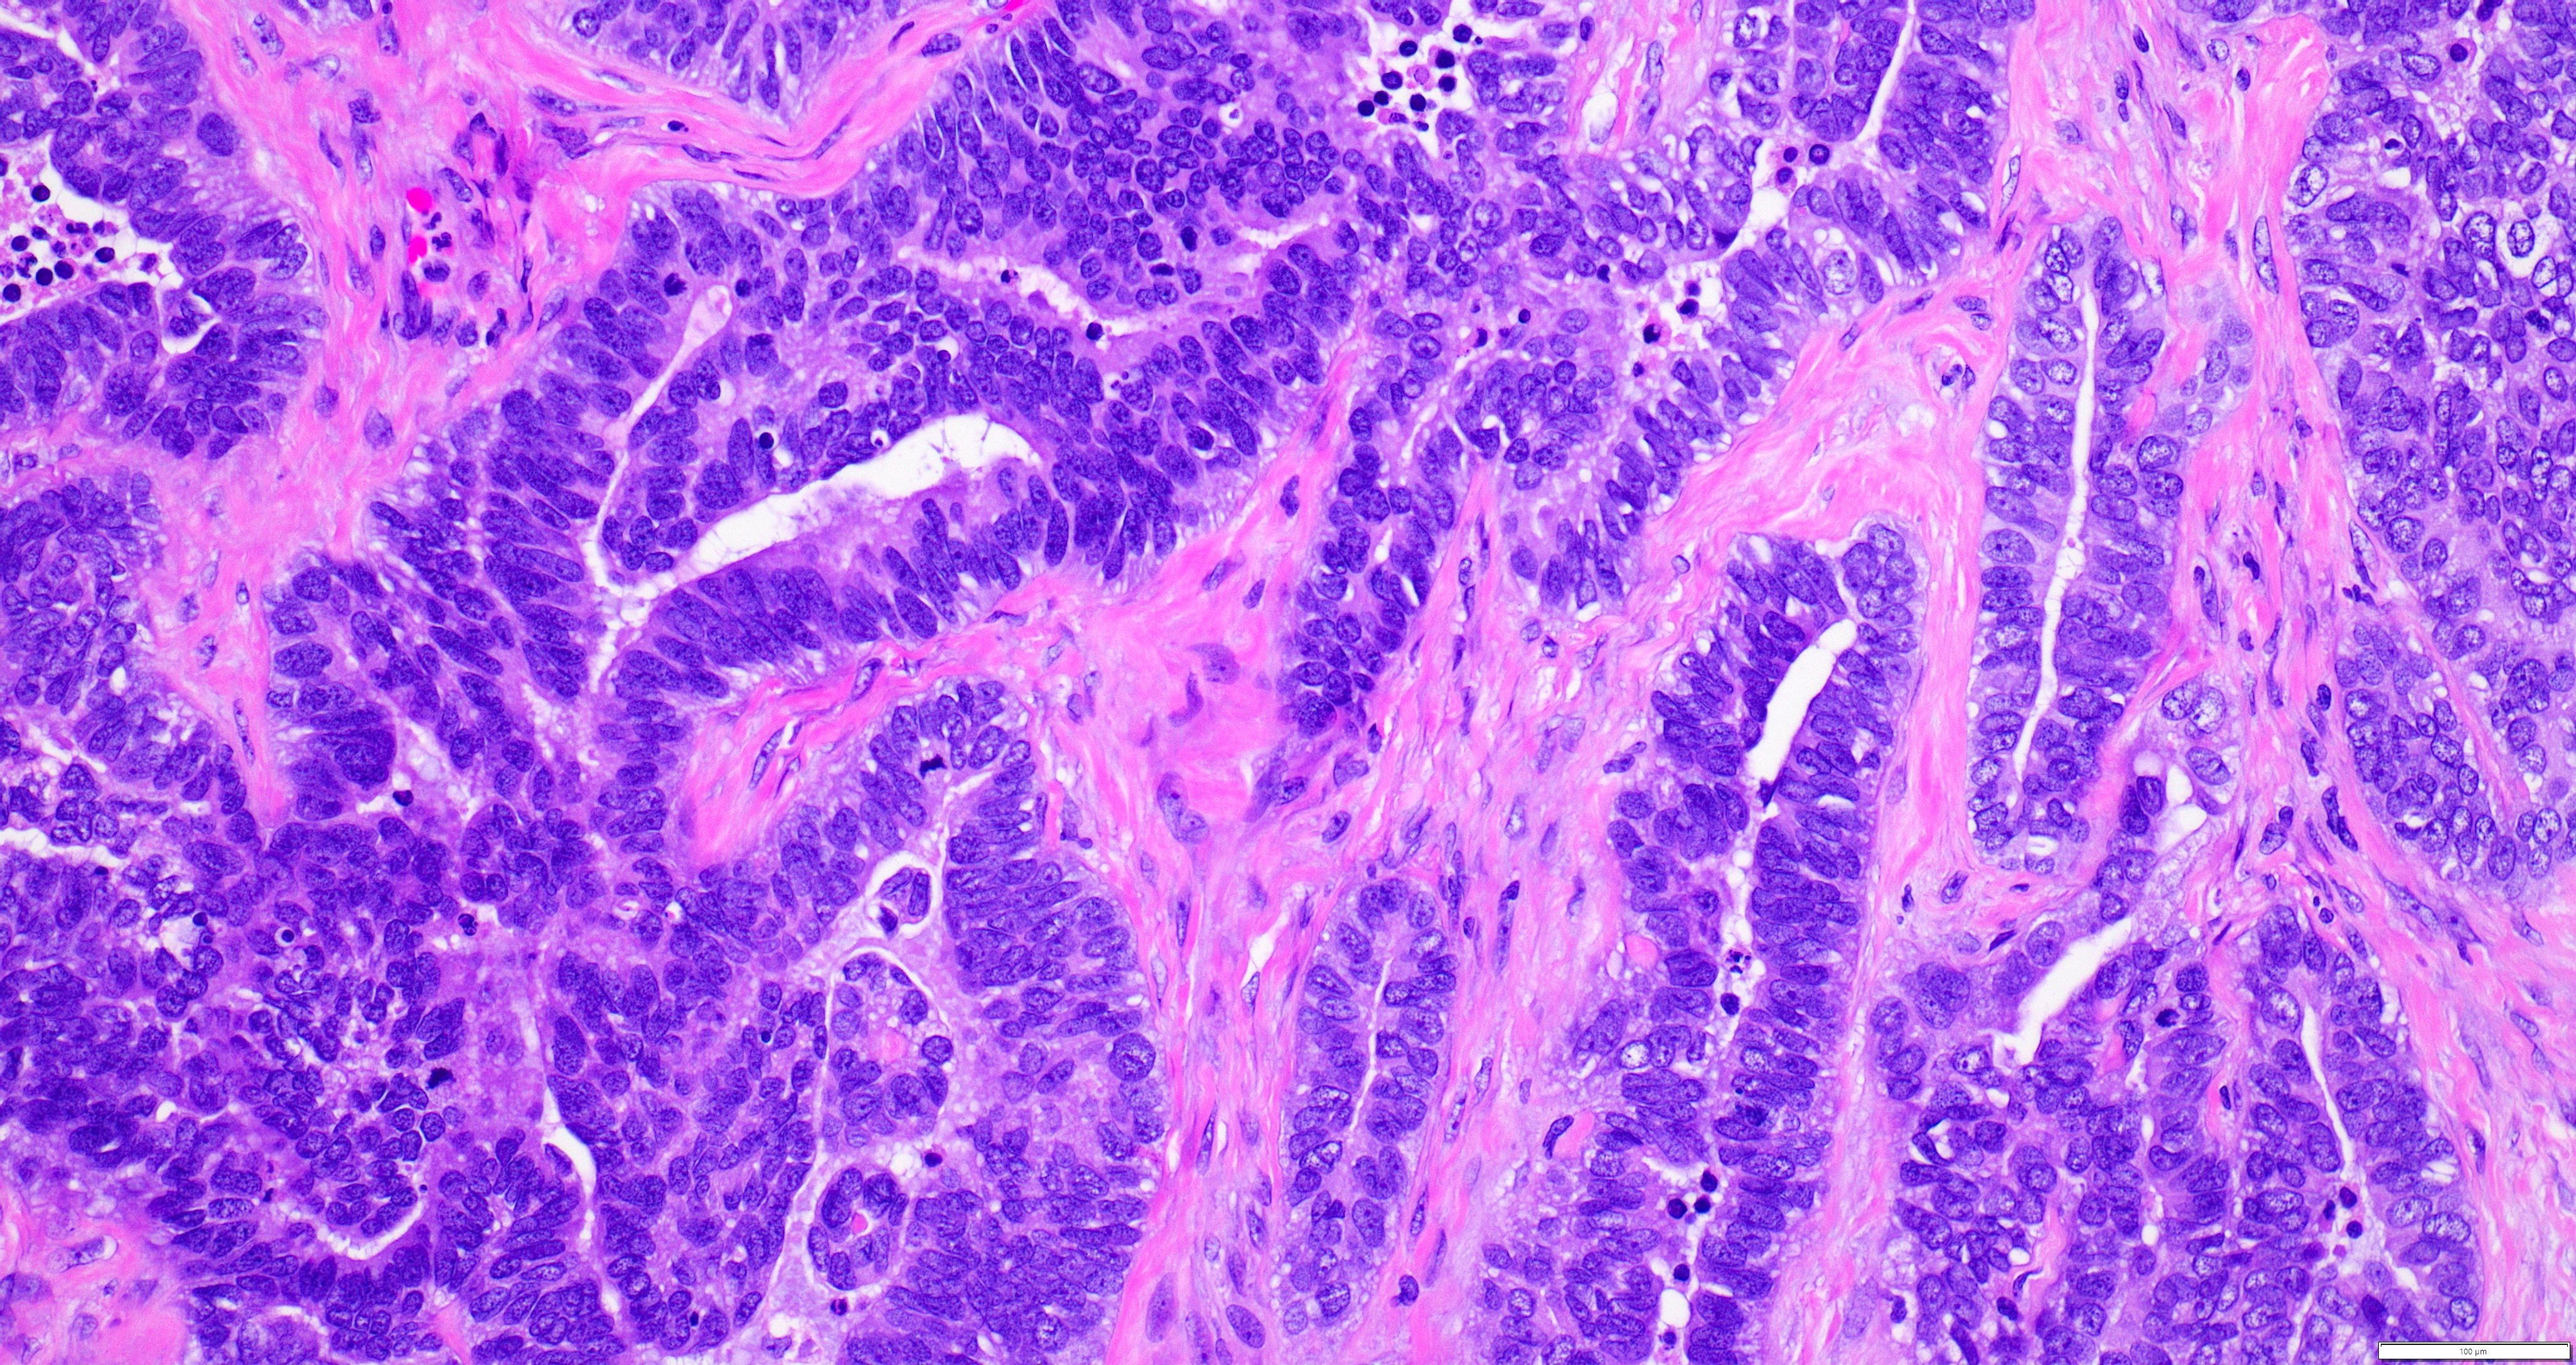

- Variety of histologic patterns that may be present within the same tumor

- Most frequently small tubules with ductal / glandular growth

- Papillary, solid growth, trabecular, retiform, sex cord-like, sieve-like, glomeruloid and spindle cell areas have all been described

- Luminal eosinophilic secretions are characteristic but not always identified

- Tumor cells can be flattened, cuboidal or columnar with mild to moderate cytological atypia

- Clear cell features can be seen but are less common

- High grade cytological atypia is usually not a predominant feature

- Nuclei show vesicular chromatin and nuclear grooves

- Sarcomatoid transformation has been seen in rare instances

- Squamous, ciliated or mucinous differentiation (metaplasia) are not present and there are no associated mesonephric remnants (J Clin Med 2021;10:698)

Microscopic (histologic) images

Contributed by Daniel Graham, M.D., Adele Wong, M.B., B.Ch., B.A.O. and Lucy Ma, M.D.